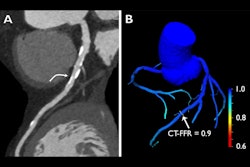

Researchers at the University of Freiburg in Germany have a longstanding reputation in cardiac imaging research, so their new study on coronary artery disease is bound to attract plenty of interest. Check it out here.